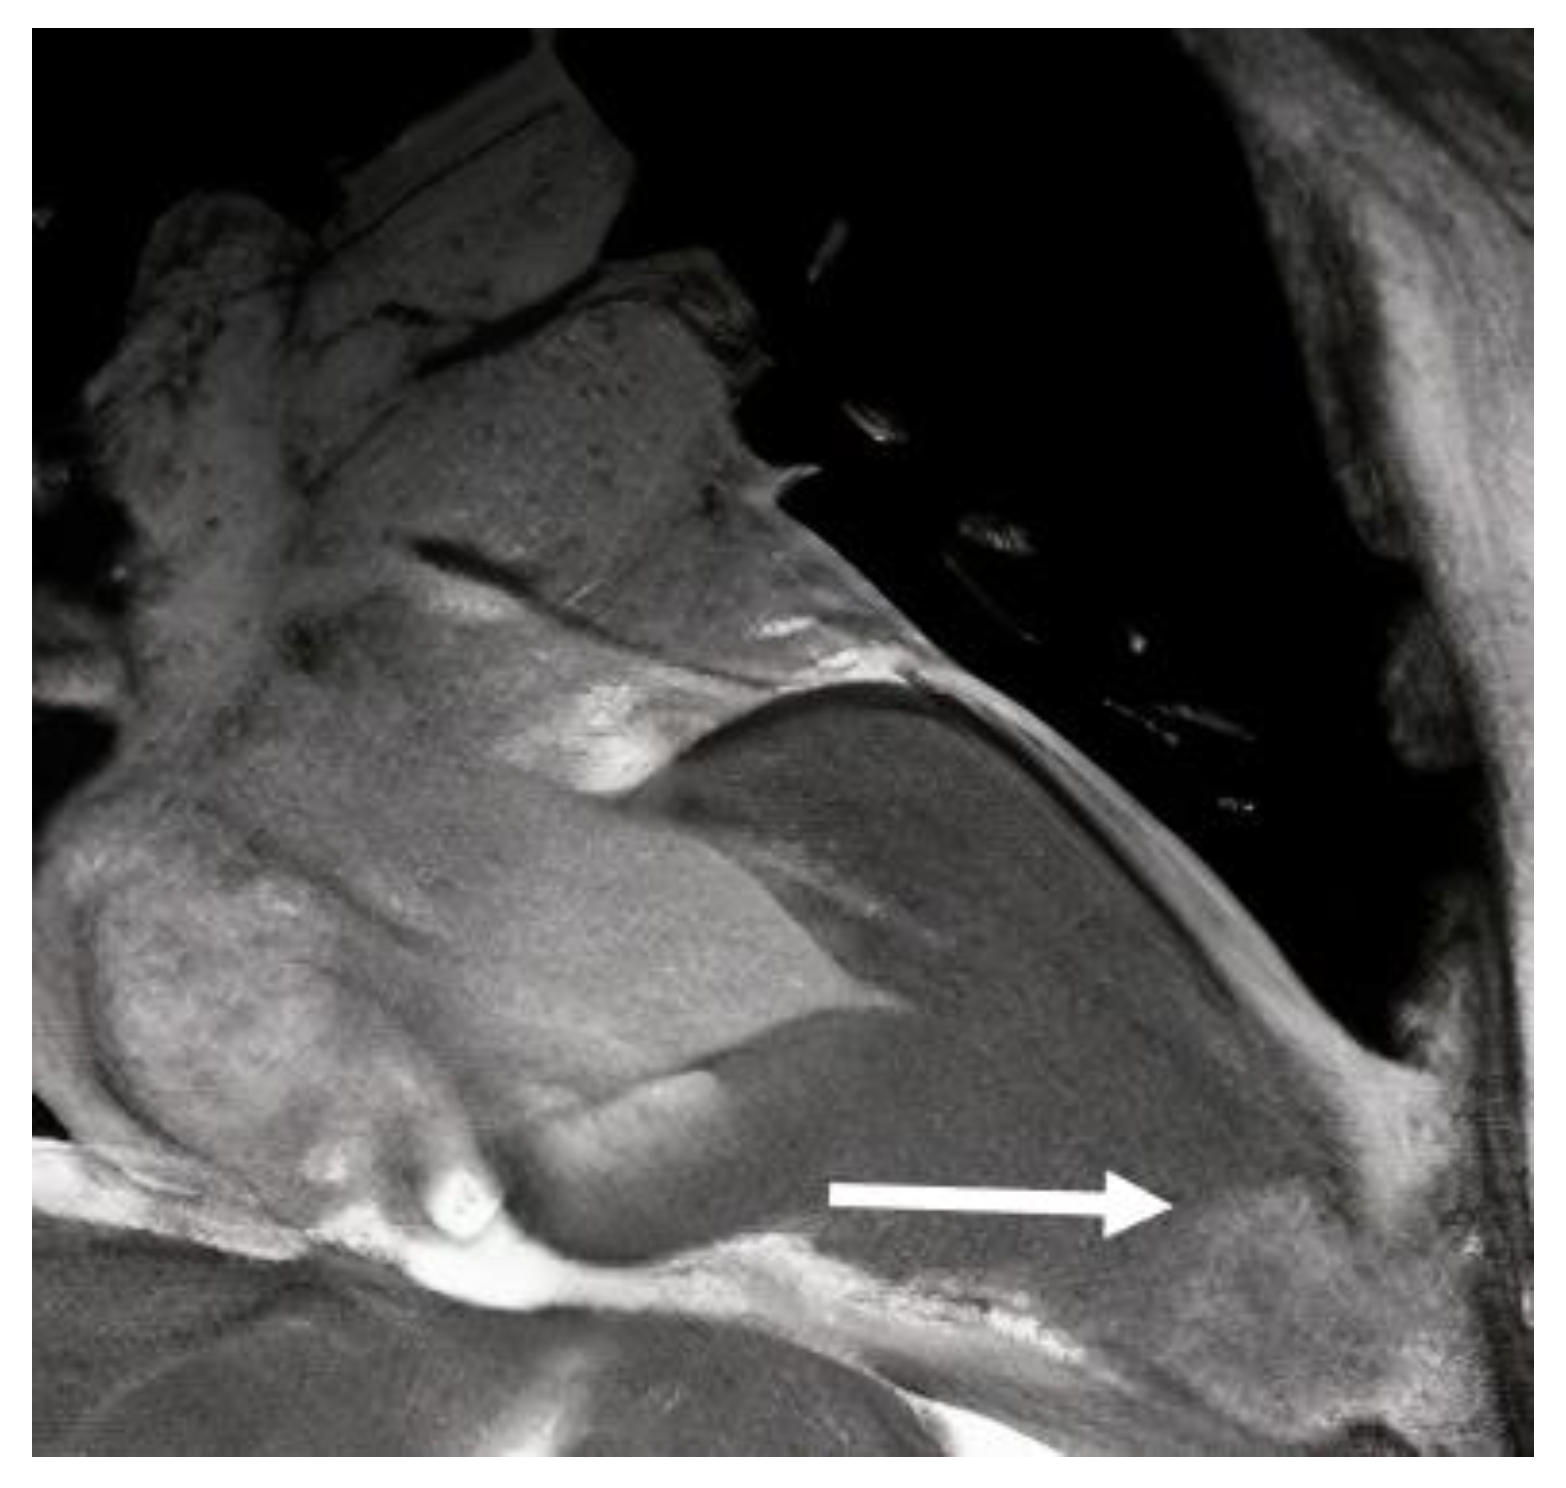

2. Mechanism of LV Aneurysm Formation in HCM

3. Diagnosis of LV Aneurysm in HCM